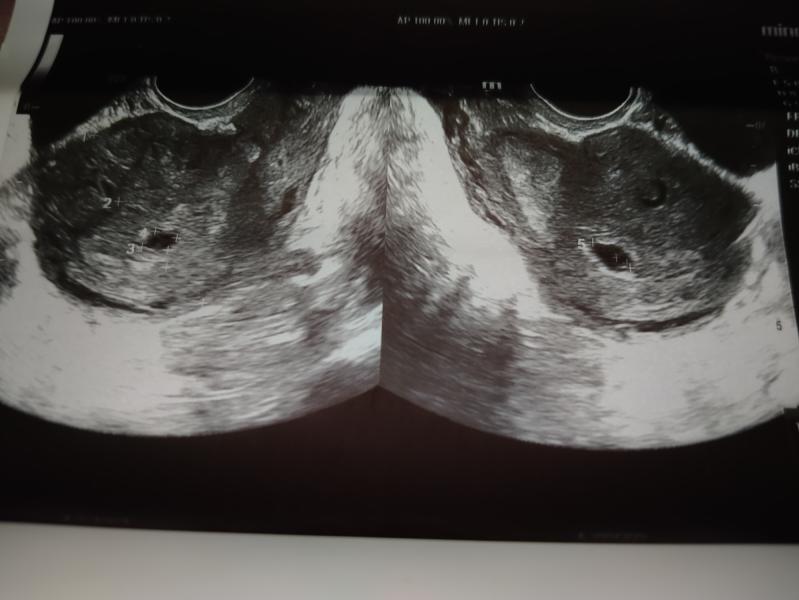

@yanaalex, @kapamelb, желтое тело при двойне может быть одно, просто ваша женская яйцеклетка после оплодотворения поделилась на двое, а так по узи вижу 2 четких кружочка, я так понимаю это 2 плодных яйца, либо я ошибаюсь)

А сколько желтых тел?